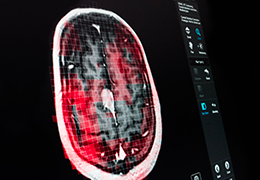

Statistical Analysis

BrainVoyager performs a wide range of statistical analyses including; parametrical mapping, contribution maps, Independent Component Analysis (ICA), Region-of-interest analysis and Event-related fMRI analysis. specifications.

Visualization Tools

Parametric and non-parametric statistical maps may be superimposed both on the original functional scans as well as onto T1-weighted 2D or 3D anatomical reference scans. Time courses of selected regions-of-interest (ROIs) are available both in 2D and 3D representations. Statistical maps may be computed either in the 2D or 3D representation since structural as well as functional 4D data (space x time) are transformed into Talairach space. This allows you to compare activated brain regions across different experiments and across different subjects